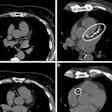

Koons and colleagues developed and assessed the performance of a CNN called Improved LUMEN visualization through Artificial super-resoluTion imagEs (ILUMENATE) in a study that included 30 patients who underwent coronary CTA. The patients were scanned with a conventional CT system as well as an ultrahigh resolution PCCT system on the same day. Of these 30 exams, eight were used to train the CNN and 22 were used as a test set to assess the algorithm's performance. Two cardiovascular radiologists who were blinded to image type compared the conventional exams to the ILUMENATE exams for overall quality, sharpness (with 1 equal to worst and 5 equal to best), and noise (1 equal to worst and 4 equal to best).

The two readers identified stenotic lesions in 22 test patients. Koons' team reported that ILUMENATE reduced percent diameter stenosis by an average of 5.3% (p < 0.001) and that the two readers preferred ILUMENATE images in all 22 cases.

Koons and colleagues also reported that the ILUMENATE exams demonstrated better image quality, sharpness, and decreased noise:

| Image quality (scale, 1 to 5) | 3.5 | 3.9 |

| Sharpness (scale, 1 to 5) | 2.9 | 3.9 |

| Noise (scale, 1 to 4) | 3 | 3.9 |

| Image quality (scale, 1 to 5) | 3.9 | 4.7 |

| Sharpness (scale, 1 to 5) | 3.1 | 4.9 |

| Noise (scale, 1 to 4) | 3.4 | 4 |